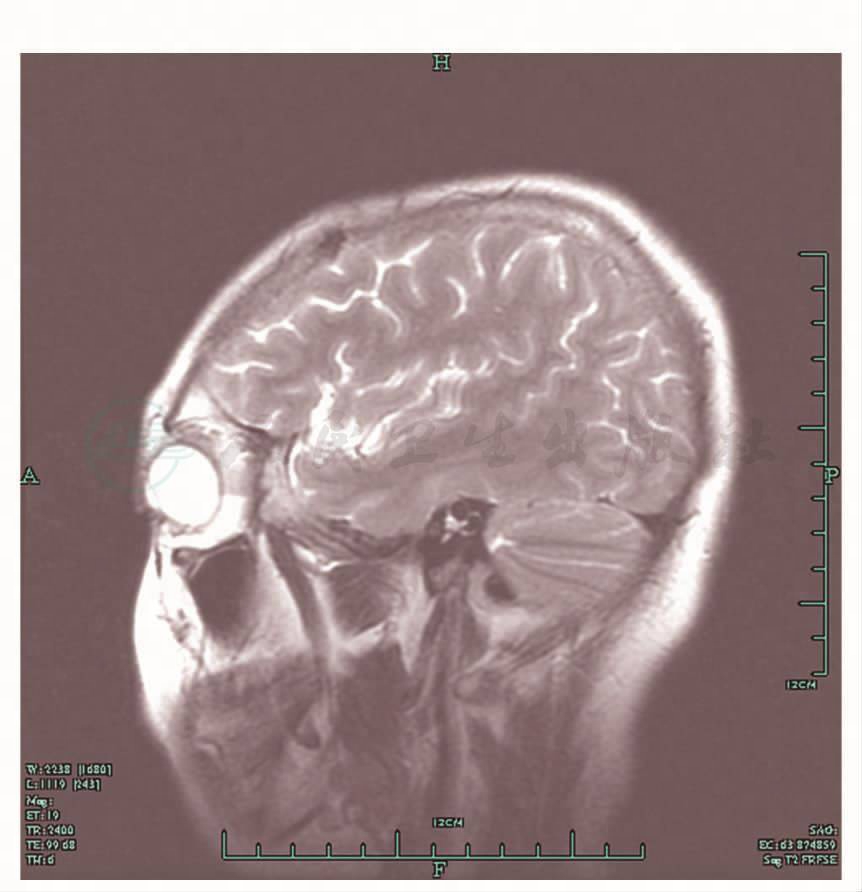

头颅MRI示脑干、左侧顶叶、右侧小脑半球内多发病变,左侧颞叶及局部脑膜异常强化(图5,图6)。

图6 MRI,颞叶病灶

治疗和转归:两性霉素B、氟康唑、氟胞嘧啶三联治疗35天,累计两性霉素B达1060mg。并给予胸腺肽皮下注射治疗。患者头痛、发热等症状均缓解,皮下结节明显减小,右腰背部结节低于皮面,大小为2.5cm×1cm;左腋前处皮下结节缩小至1cm×0.5cm;右肩胛下角结节消失。复查头颅MRI示颅内多发病变及左侧颞叶病变治疗后基本吸收(图8,图9)。

图9 治疗后MRI